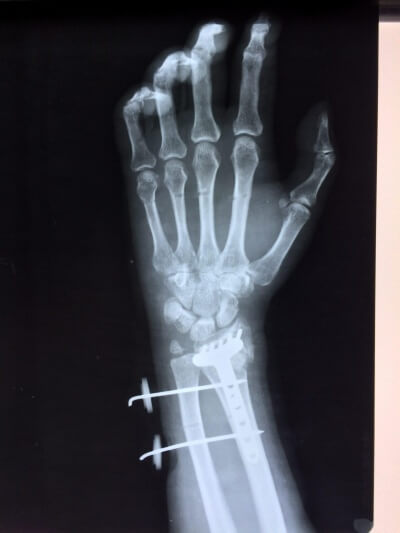

Использование материала Остеоматрикс при полифокальном внутрисуставном импрессионном переломе дистального эпиметафиза лучевой кости